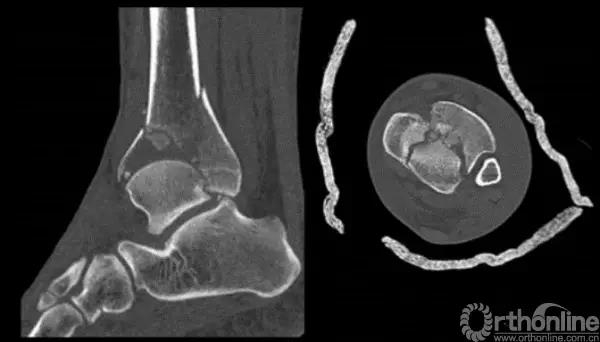

Pilon骨折手术入路选择原则一般取决于最适合进行关节面复位的入路。cole在2013年jot发表的文章描述了pilon骨折的骨折线图根据多例病例汇总到一起,颜色越深则越骨折线经过的可能性越大。

他将pilon骨折大致的骨块进行了分类,分别为后、前内、前外三个骨折块。Pilon骨折的入路一共有5个,前内、前正中、前外、后内、后外。

1. 粉碎的骨折

针对该类骨折一般采取小块靠大块的原则,充分显露之后,先从后面开始,逐步把小块往大块上复位,逐渐复位到最前面。